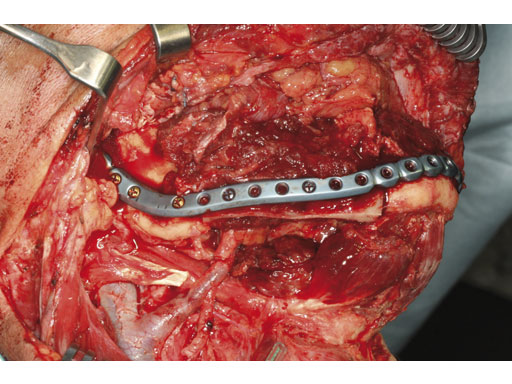

Case 1: A 27-year-old woman with an odontogenic myxoma in the left mandible. The preformed reconstruction plate was inserted prior to the tumor resection using a transoral approach with only a small additional transbuccal incision. To date the patient is free of symptoms with no signs of hypoaesthesia of the mandible and no signs of relapse. After another relapse-free period dental implants are planned for oral rehabilitation.

Fig 1 ad Transoral application of preformed reconstruction plate before tumor dissection.